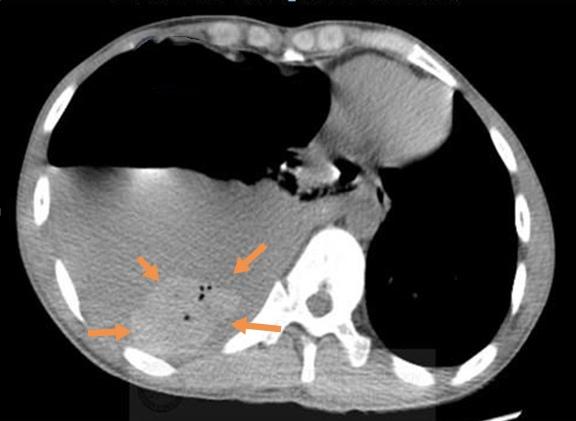

胸部CT显示右侧液气胸,胸腔积液和气体压迫肺组织,导致呼吸困难和不能深吸气,并且挤压心脏向左侧移位。

在大量灰色的胸水里,有一块椭圆形的小团块沉在水底,里面还有4个小气泡。

这个病人不是单纯的液气胸,准确点说,他是自发性血气胸,出血量在400ml以上了。